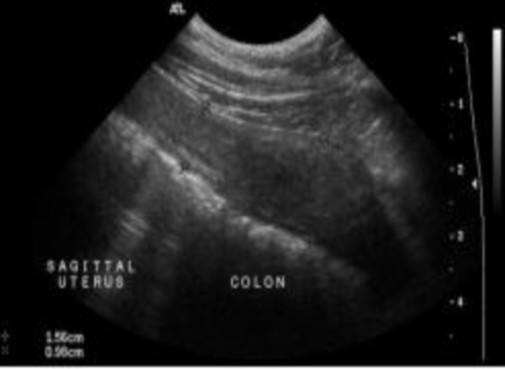

Hình 2.6. Hình ảnh giai đoạn trước động dục ở giống Labrador Retriever 6 tuổi

Nguồn: Rachel Pollard & Silke Hecht (2015)

Bàng quang chứa đầy nước tiểu hoạt động như một cửa sổ âm để cải thiện hình ảnh tử cung. Vì vậy, không nên để cho chó đi tiểu trước khi tiến hành siêu âm. Tử cung bình thường được định vị tốt nhất bằng cách quét ngang giữa bàng quang tiết niệu và đại tràng. Cổ tử cung và thân tử cung được nhìn thấy theo chiều ngang như một cấu trúc hình bầu dục giảm âm liên tục ở mặt lưng đến bàng quang tiết niệu và bụng đến đại tràng hình lưỡi liềm.